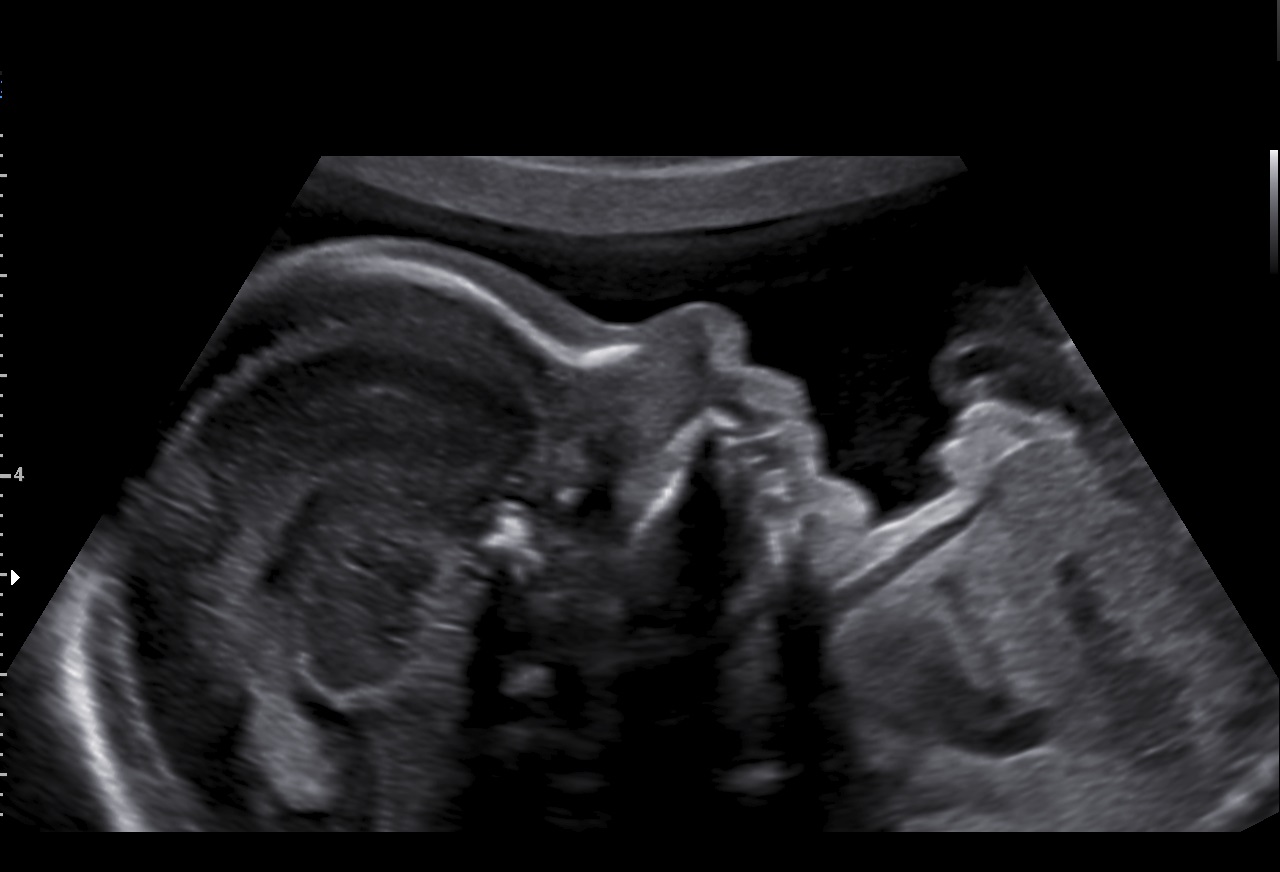

Le RealisticVue™ propose des rendus anatomiques de haute résolution en 3D/4D. Une source lumineuse est modélisée afin de permettre un effet d'ombre sur les structures et de surligner les zones d'intérêt.

Le filtre de réduction de bruit ClearVision améliore les contours d'une structure anatomique et augmente le rapport signal sur bruit. Il permet de délivrer des images 2D plus nettes et augmente la différenciation tissulaire.